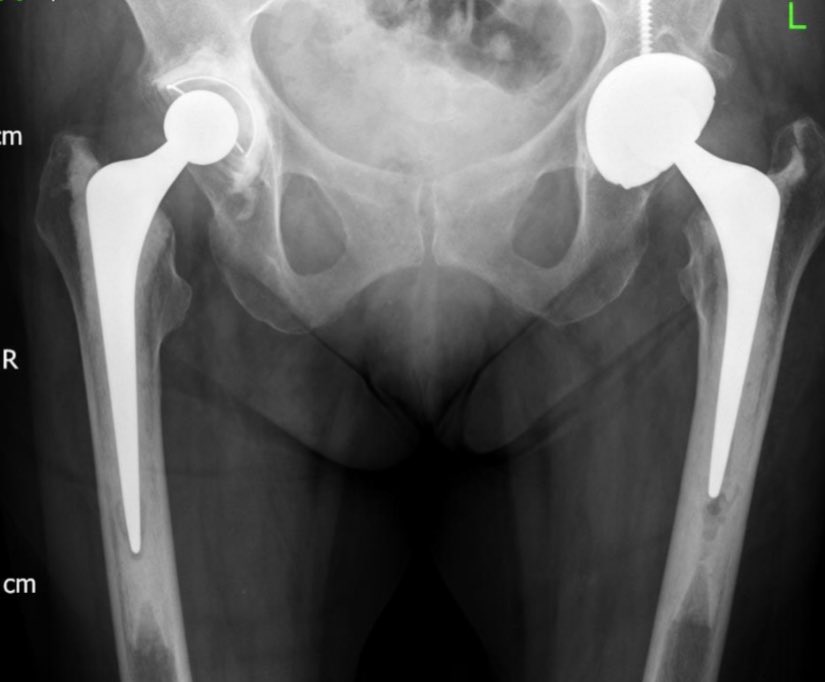

On the femoral side, it’s interesting. The stem has been sunk in (the SID) similar (perhaps sl less) than the other side yet there is still a marked LLD. Perhaps some previous femoral issue. Regardless to correct the lengths, the stem needs to be sunk further into the mantle.

In order to do this the 44/00 in-cement stem is ideal. 25mm shorter than standard and small enough to fit into the mantle of a 0 stem. So some careful templating of the new SID helps here.